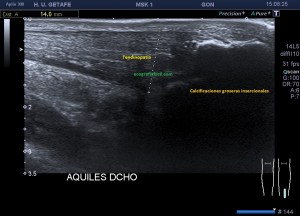

6

Imágenes de calcificaciones groseras, distróficas, con su sombra acústica posterior, superficiales y profundas, con diferentes tipos de tamaños. En la imagen 7 las ves en eje corto.

Desde la inserción hasta el origen el aquiles es muy largo, usar imagen panorámica nos ayudará a tener una idea global de todo el tendón, la orografía es complicada, no es facil el apoyo, el tendón es muy fino, y el recorrido de todo el tendón requiere técnica, tiempo…básicamente, no desesperes. En la imagen 9 tienes una panorámica con la gran cantidad de calcios distróficos que afectan a este tendón.

10

Podemos encontrar calcificaciones muy groseras, insercionales y no insercionales, con tendinopatía asociada, como ves en la imagen 10.